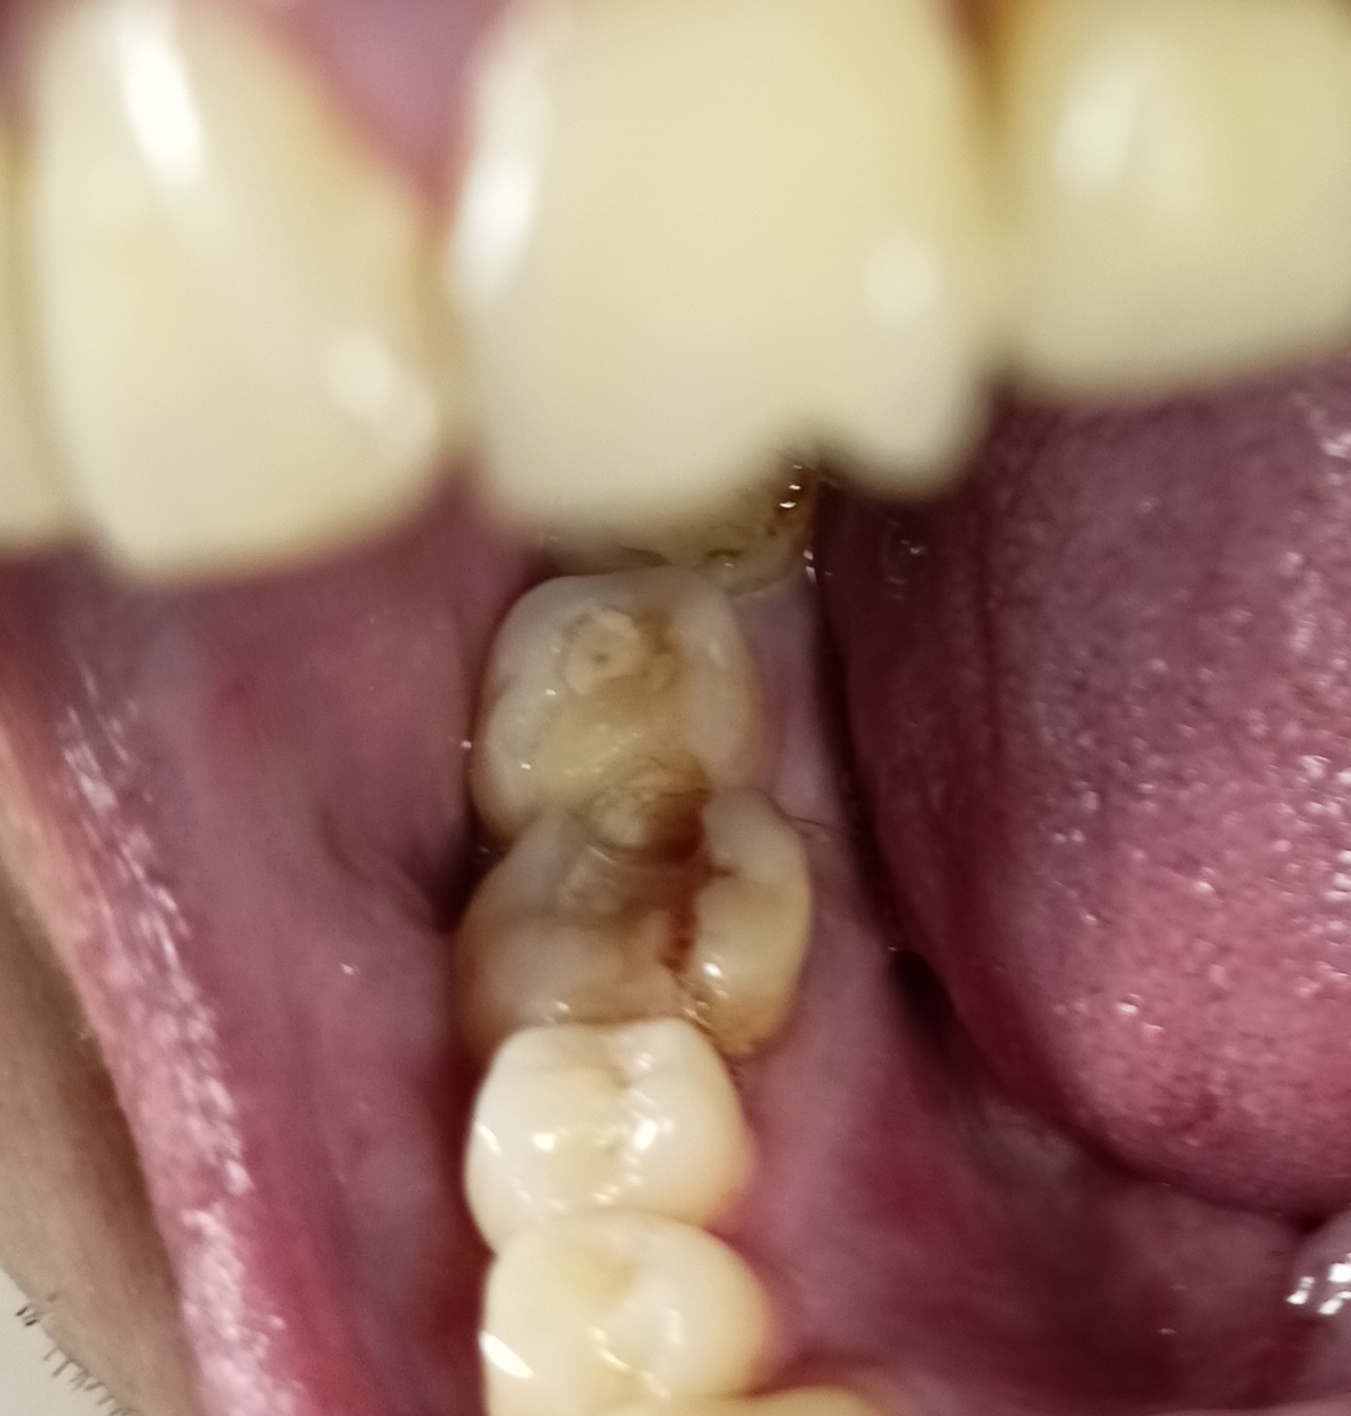

Зуб пятерка. Возможно такое вылечить, анонче? Отклолся как то, вообще не болит.

Аноним 11/08/25 Пнд 15:56:42 1635620 36

1754917002022.jpg 1515Кб, 3968x2976